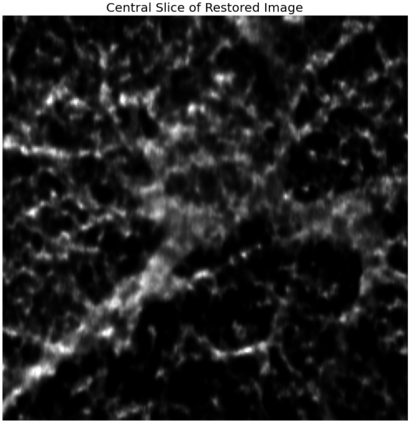

The quality of microscopy images often suffers from optical aberrations. These aberrations and their associated point spread functions have to be quantitatively estimated to restore aberrated images. The recent state-of-the-art method PhaseNet, based on a convolutional neural network, can quantify aberrations accurately but is limited to images of point light sources, e.g. fluorescent beads. In this research, we describe an extension of PhaseNet enabling its use on 3D images of biological samples. To this end, our method incorporates object-specific information into the simulated images used for training the network. Further, we add a Python-based restoration of images via Richardson-Lucy deconvolution. We demonstrate that the deconvolution with the predicted PSF can not only remove the simulated aberrations but also improve the quality of the real raw microscopic images with unknown residual PSF. We provide code for fast and convenient prediction and correction of aberrations.